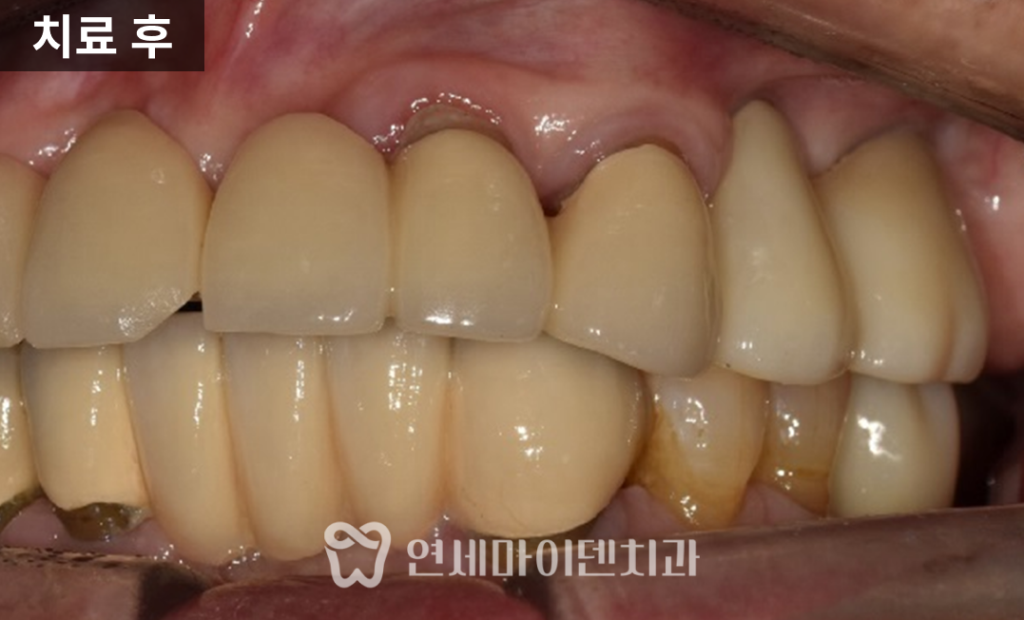

치료 후 가장 큰 변화는 ‘식사’

임플란트를 마무리한 이후,

어머님은 해당 부위로 다시 식사가 가능해졌습니다.

치료 전에는 한쪽으로도 식사가 쉽지 않았지만,

치료 후에는 음식물을 씹는 데

큰 불편이 없다고 말씀하셨습니다.

6개월 이상 경과 관찰에서도

상태는 안정적으로 유지되고 있으며,

위생 관리 방법에 대한 교육과

정기적인 체크업을 병행하며 관리 중입니다.